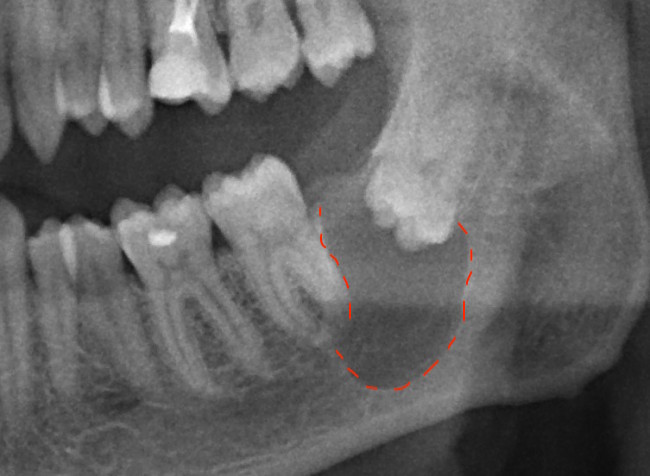

Как вы думаете, с чем пациент обратился? Нет, не с дикой болью или отеком, как многие могли подумать. А вот с чем — «Чет у меня еда забивается снизу справа, посмотрите.» То есть молодого человека беспокоит лишь то, что забивается еда… просто забивается еда, Карл! На вопрос, а болело ли? Ответ — «Да нет, никогда не болело и ничего не беспокоило.» Ну… порядок действий в этом случае вы уже знаете. Вот вам и — «подожду, пока не забеспокоит».

Если вы думаете, что это самое страшное, что может вас ожидать, как бы не так.

Вот такие кисты (а это еще не самая большая) могут расти в вашей челюсти и никак вас не беспокоить. Естественно зуб нужно удалять. Во избежании увеличения данного новообразования, и возникновения возможных осложнений. Перед этим каналы в соседнем 7ом зубе нужно пролечить, так как его корни находятся в просвете кисты.

Проблема решена. Пациент счастлив. А ведь всего этого можно было избежать, сходив планово на осмотр к стоматологу.

Вот такая картина нас ждала спустя год после удаления. Все затянулось. Все прекрасно!

А грозить это могло как переломом челюсти, так и поражением нижнечелюстного нерва, которое сопровождается онемением губы и подбородка со стороны причинного зуба, а онемение это может остаться на всю жизнь.